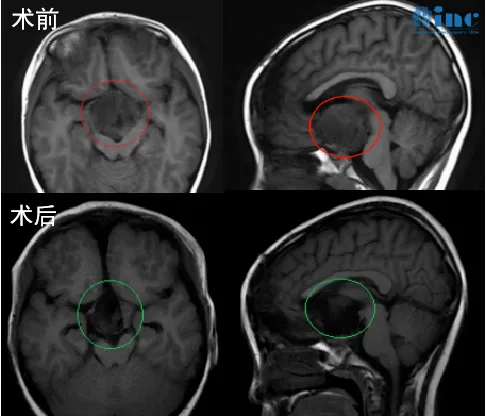

年僅8歲的小偉要面臨人生中的第二次開顱手術(shù) 視神經(jīng)膠質(zhì)瘤復(fù)發(fā) 原本水汪汪的大眼睛現(xiàn)在也變得混沌 僅能看到一絲光亮 父母一直在感慨走錯路了 為何第一次手術(shù)沒有做好萬全準(zhǔn)備?...

視神經(jīng)膠質(zhì)瘤治療較好的是什么辦法?早期手術(shù)切除聯(lián)合術(shù)后放射治療可明顯好轉(zhuǎn)OPG患者預(yù)后,程度上能夠降低腫瘤復(fù)發(fā)率。...